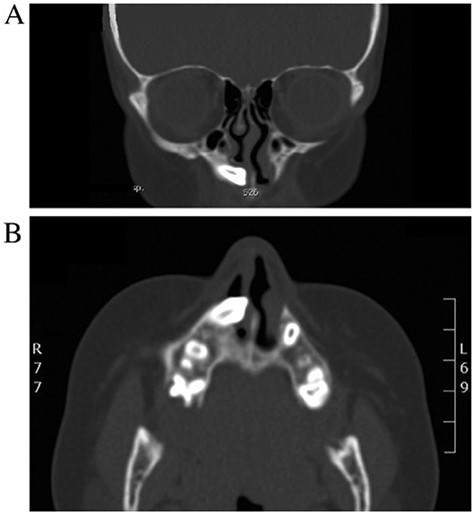

A 19-years-old male presented to otolaryngology clinic facial pain over the upper jaw area along with post-nasal discharge for 6 months. Patient gave history of recurrent sinusitis; otherwise, he is medically and surgically free with no history of trauma. Examination showed septal spur to the left side with no other significant findings. CT scan of the paranasal sinuses showed bilateral ectopic teeth and cystic lesions within both of the maxillary sinuses (Fig. 5). Patient was managed with endoscopic endonasal enucleation of the cysts and extraction of the ectopic impacted teeth through middle meatal antrostomies. Histopathology confirms the diagnosis of dentigerous cysts. Post operatively, the patient symptoms resolve completely, and she remained symptoms free over 5 years follow up.

CT scan of the paranasal sinuses showed bilateral ectopic teeth and cystic lesions within both of the maxillary sinuses.